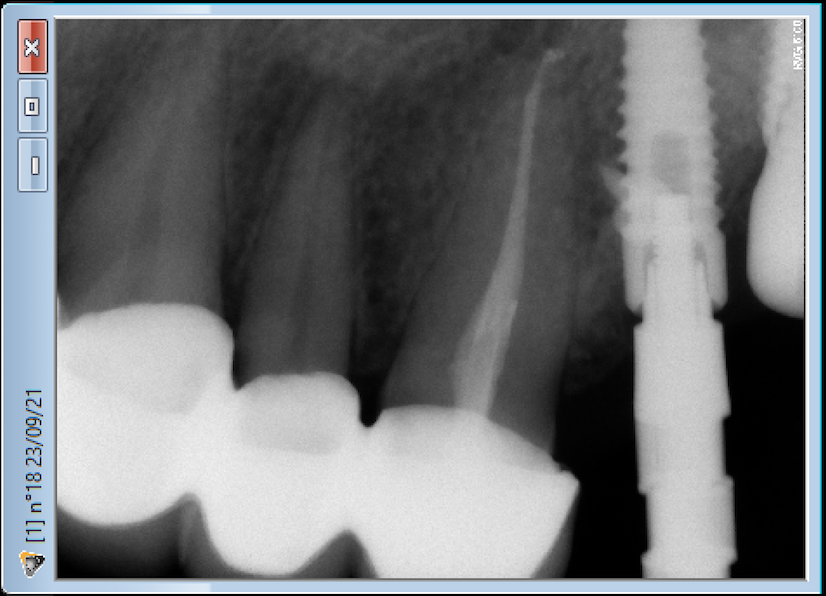

Buenos días. OS adjunto las fotografías de las periapicales de un implante colocado en la pieza 24, para que me ayudéis con la identificación.

Veo que has probado un transfer de anyridge. ¿Tendrías una foto de la conexión del pilar que llevaba? Me imagino que habrás visto que no es un hexágono interno, pero es que tengo dudas de si lo que se ve es un bisel de esa conexión o pudiera ser una conexión tipo novel active.

Se trata de un implante BTK de 4 mm de diámetro.

La plataforma que tiene es de la conexión interna tipo Zimmer de 3.5 mm. Métrica de tornillo 1.8 mm. Destornillador 1.2 mm hexagonal.